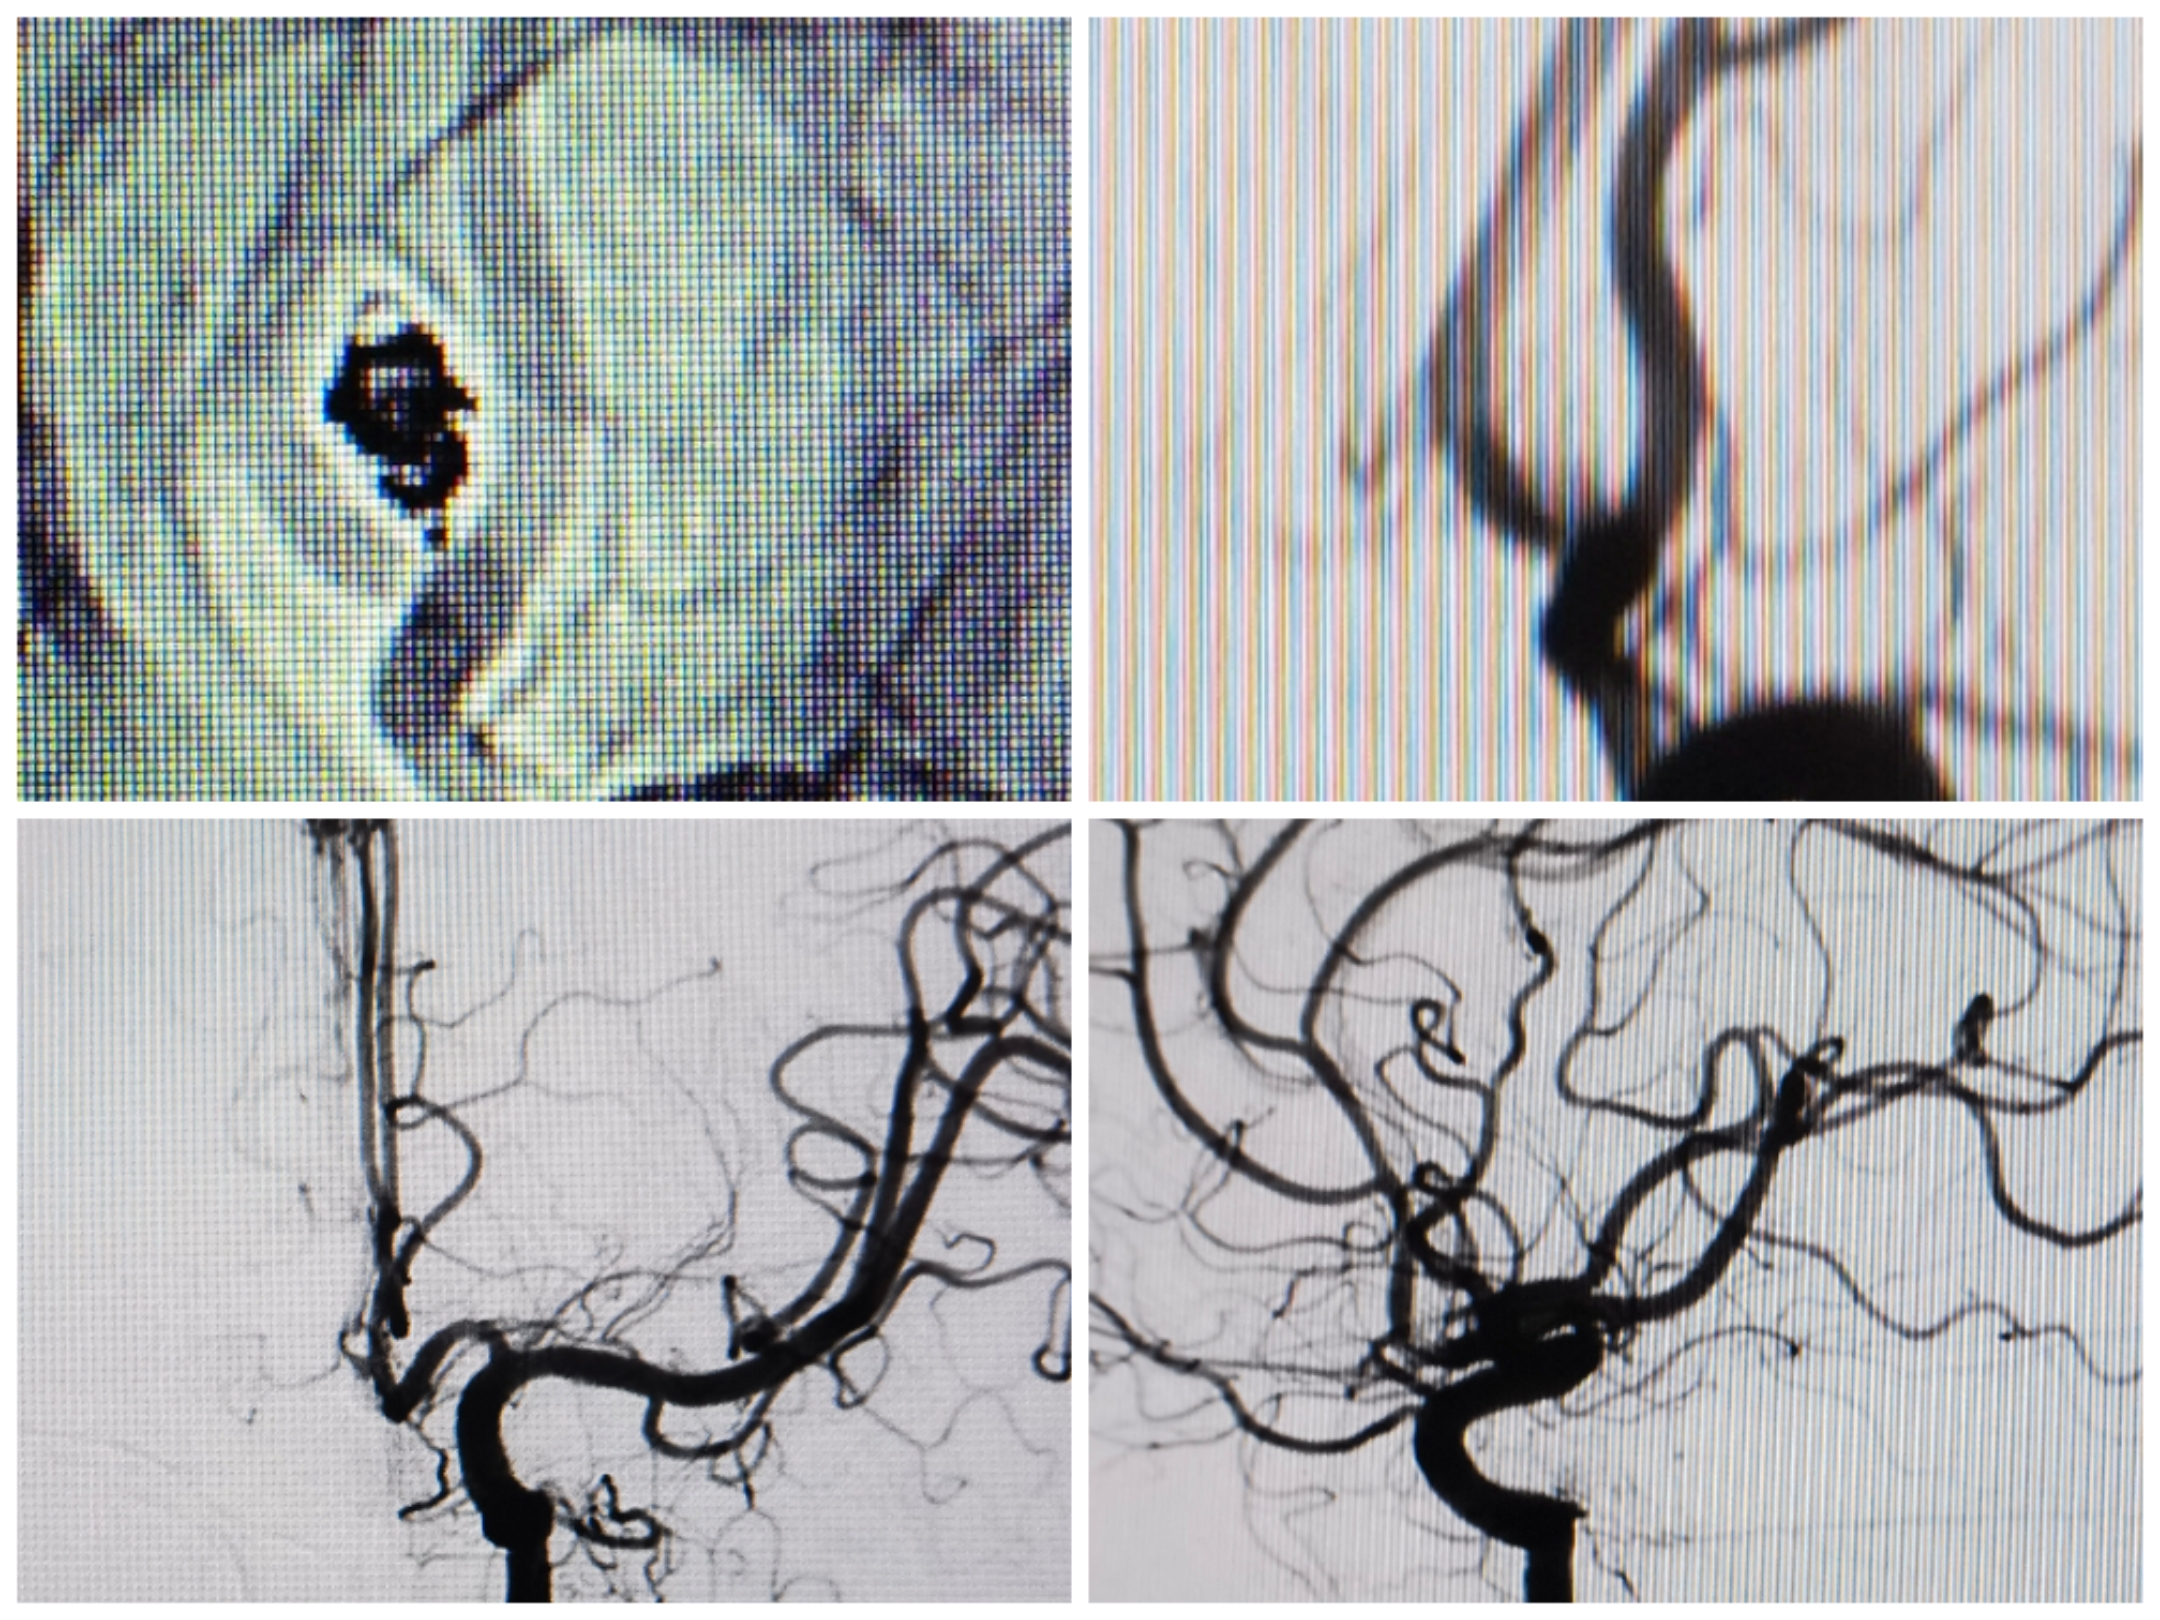

3D重建提示宽颈前交通动脉瘤,瘤颈偏向同侧A2。手术计划:支架置入同侧A2,利用开环支架穹窿效应保护对侧A2,行弹簧圈栓塞。WEB也是个不错的选择,可惜手上没有材料。

术后栓塞情况:支架开放良好,弹簧圈致密栓塞,双侧大脑前血流良好

术后3D重建情况